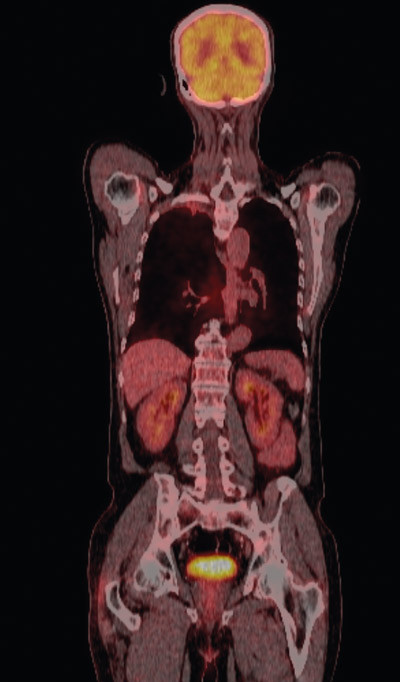

Fire uker etter avsluttet behandling ble pasienten reinnlagt til operativ behandling med kurativ intensjon. Ny MR collum/thorax viste fortsatt sannsynlig innvekst i 2. og 3. høyre costa samt mulig tumoraffeksjon av Th 2. Det var ikke tegn til affeksjon av plexus brachialis. CT viste at tumor hadde skrumpet (fig 2c, d). Det ble også utført PET-CT (fig 4). Denne var uegnet til vurdering av lokale forhold pga. pasientens nylig gjennomgåtte strålebehandling, men viste ingen tegn til viabelt tumorvev i thoraxveggen eller malignitet andre steder i kroppen. Basert på PET-CT-funnene ble pasienten etter tverrfaglig vurdering bedømt som operabel, og det ble gjennomført lobektomi av høyre overlapp.